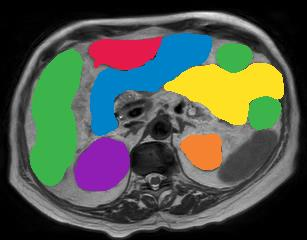

Vision transformers, with their ability to more efficiently model long-range context, have demonstrated impressive accuracy gains in several computer vision and medical image analysis tasks including segmentation. However, such methods need large labeled datasets for training, which is hard to obtain for medical image analysis. Self-supervised learning (SSL) has demonstrated success in medical image segmentation using convolutional networks. In this work, we developed a \underline{s}elf-distillation learning with \underline{m}asked \underline{i}mage modeling method to perform SSL for vision \underline{t}ransformers (SMIT) applied to 3D multi-organ segmentation from CT and MRI. Our contribution is a dense pixel-wise regression within masked patches called masked image prediction, which we combined with masked patch token distillation as pretext task to pre-train vision transformers. We show our approach is more accurate and requires fewer fine tuning datasets than other pretext tasks. Unlike prior medical image methods, which typically used image sets arising from disease sites and imaging modalities corresponding to the target tasks, we used 3,643 CT scans (602,708 images) arising from head and neck, lung, and kidney cancers as well as COVID-19 for pre-training and applied it to abdominal organs segmentation from MRI pancreatic cancer patients as well as publicly available 13 different abdominal organs segmentation from CT. Our method showed clear accuracy improvement (average DSC of 0.875 from MRI and 0.878 from CT) with reduced requirement for fine-tuning datasets over commonly used pretext tasks. Extensive comparisons against multiple current SSL methods were done. Code will be made available upon acceptance for publication.